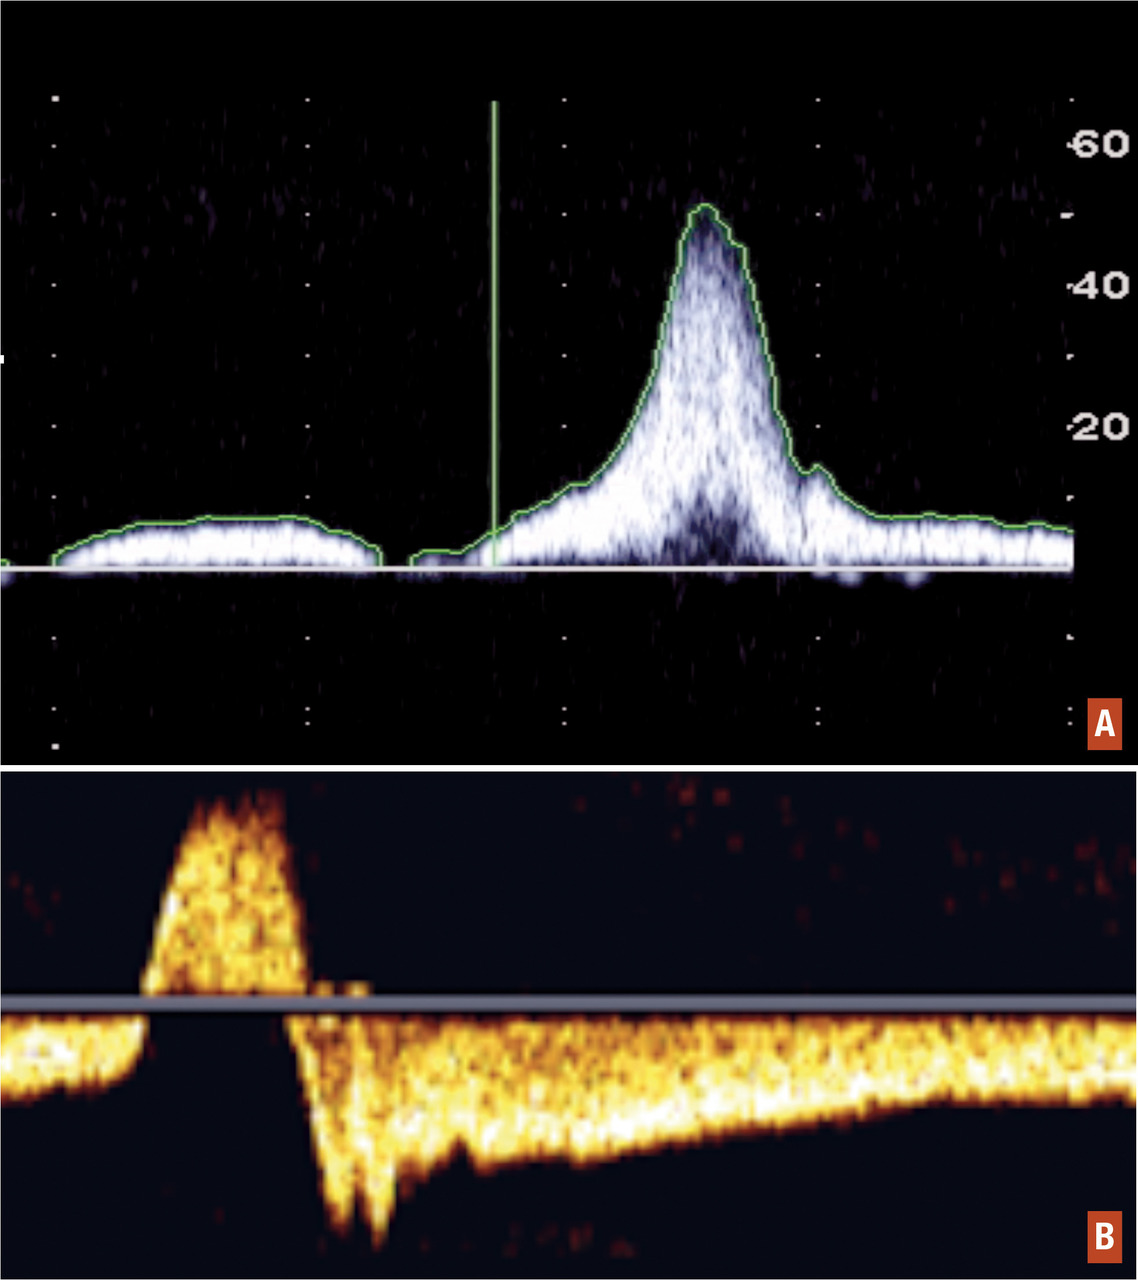

Doppler continu

Cet examen, moins réalisé de façon isolée de nos jours avec le développement des appareils écho-Doppler, peut être réalisé en même temps que l’examen clinique. Il permet de mettre en évidence un reflux veineux pathologique (par insuffisance valvulaire ou ostiale), une incontinence au niveau des perforantes et une possible obstruction.

Écho-Doppler veineux

Cet examen représente la méthode de choix pour diagnostiquer un reflux veineux ou mettre en évidence un syndrome obstructif. Il se pratique initialement en décubitus dorsal pour l’exploration morphologique, à la recherche d’une avalvulation profonde, de séquelles post-thrombotiques ou de malformations veineuses, puis en position debout, sur l’escabeau de phlébologie, pour l’exploration hémodynamique du réseau veineux superficiel, sans oublier les jonctions saphéno-fémorale, saphéno-poplitée et les veines perforantes. Il confirmera le diag­nostic de varice, permettra de mesurer les diamètres veineux et de rechercher un reflux pathologique (par insuffisance valvulaire ostiale ou tronculaire) et une incontinence de veine perforante. Ainsi, de manière générale, une veine est dite incontinente si elle présente un reflux supérieur à 0,5 seconde au niveau de la grande ou de la petite veine saphène. Cet examen permet la réalisation d’une carto­graphie veineuse précise répertoriant l’état morphologique et hémodynamique du patient afin de guider la thérapeutique.